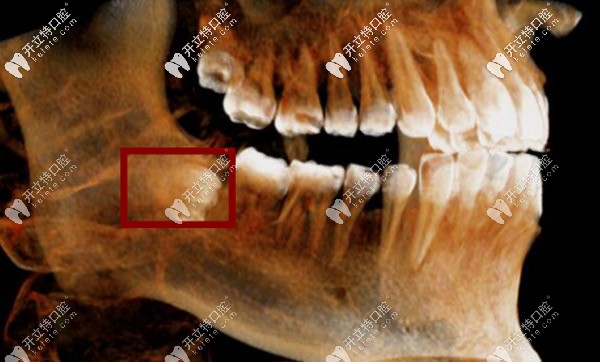

像這種就是比較復(fù)雜的智齒,有的人覺得不是很疼,但是要注意,牙根還沒有長完全,而且離神經(jīng)管較近。智齒繼續(xù)生長會(huì)壓迫前面牙齒的牙根,有的還會(huì)吸收牙根引起牙槽骨囊腫等問題。

建議向正規(guī)醫(yī)院咨詢并找經(jīng)驗(yàn)豐富的醫(yī)生進(jìn)行拔除治療。